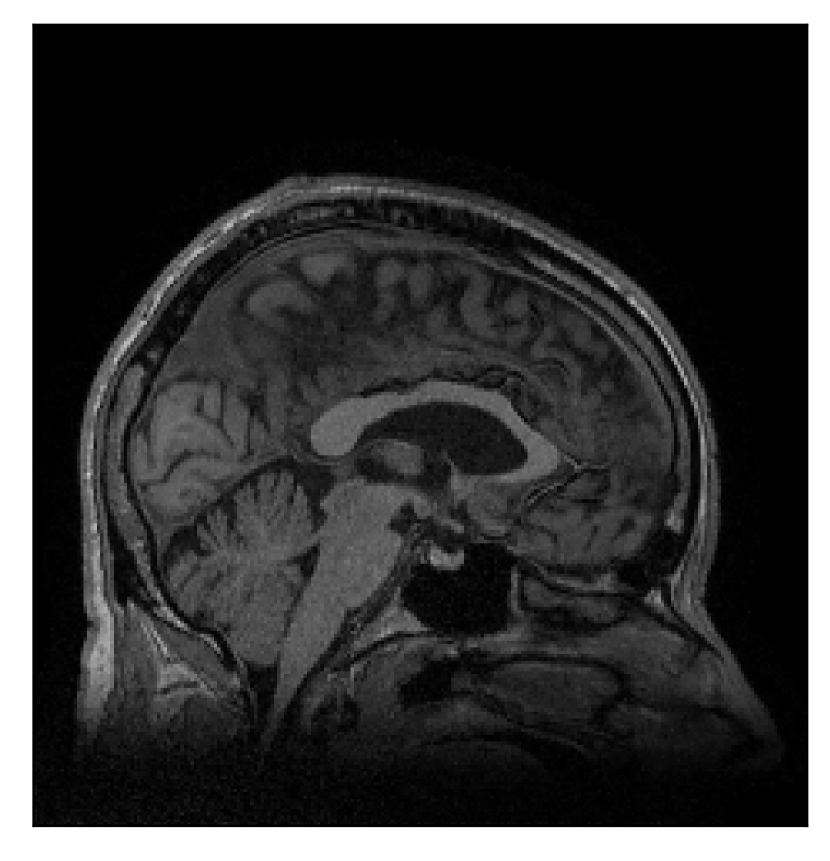

In the first experiment, we asked volunteer 3 to change position once during the prospectively-corrupted acquisition. We consider a corrupted T2-weighted contrast and a reference T1-weighted contrast (see Table 1). One important aspect of this experiment is related to the acquisition protocol of the T2-weighted contrast, based on a linear-filling pattern in -space. The corrupted data used as input for the proposed motion-correction algorithm is obtained by exporting the reconstructed volume directly from the scanner, followed by a simple Fourier transform. Note that this 3D image has been obtained by a SENSE reconstruction.

4.3 Experiment 3: scanner reconstruction vs raw k-space data

The results of the two experiments described in Section 3.3 are depicted in Figures 12 and 14. The main difference between the two experiments is related to the input data for the proposed motion-correction algorithm.

In the first experiment, the corrupted contrast has been acquired with a protocol based on a linear filling pattern in -space. Note that, in this particular case, the scanner reconstruction implements the SENSE method. We then extracted the DICOM of both amplitude and phase produced by the scanner, and used it as input data (after a Fourier transform) for the algorithm. The proposed scheme is able to successfully remove the motion artifacts in Figure 12.

| Section 3.3, Figure 12 | Sagittal | 22.26 | 27.54 | 0.6963 | 0.8409 |

| Coronal | 23.46 | 31.65 | 0.7321 | 0.8370 | |

| Axial | 24.55 | 32.33 | 0.7895 | 0.8144 | |

| Section 3.3, Figure 12 | T2 | Completely corrected | No blurring | No additional artifacts | |